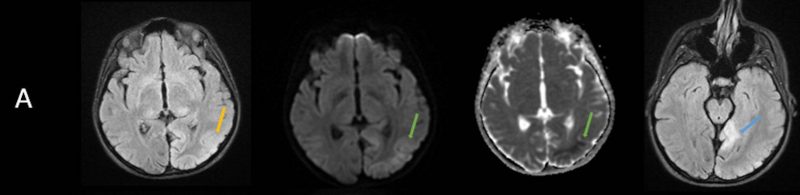

- A) Aksiyel FLAIR görüntülerde parietooksipital lobda kortikal hiperintensite (ok) ve difüzyon görüntülerde kısıtlanma alanları izleniyor (oklar). Ertesi gün çekilen kontrol MRG’de FLAIR serilerde yeni gelişen oksipital bölgede kortikal hiperintensite (ok) izlenmektedir.

- MRG’de akut fazda T2/FLAIR hiperintensiteyle birlikte giral şişme ile karakterize enfarkt-benzeri lezyonlar ve subkortikal beyaz cevher tutulumu görülür. DWI’da artmış sinyal dikkat çekmekle birlikte ADC değerlerinin normal ya da hafif artmış olması, baskın sürecin vazojenik ödem olduğunu gösterir.